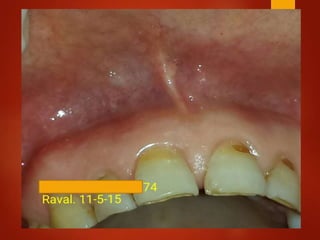

El documento es un registro médico odontológico que muestra las fechas de las visitas de un paciente al centro de salud El Raval, incluyendo exámenes y tratamientos realizados como la extracción de cálculos salivales en abril y mayo de 2012.